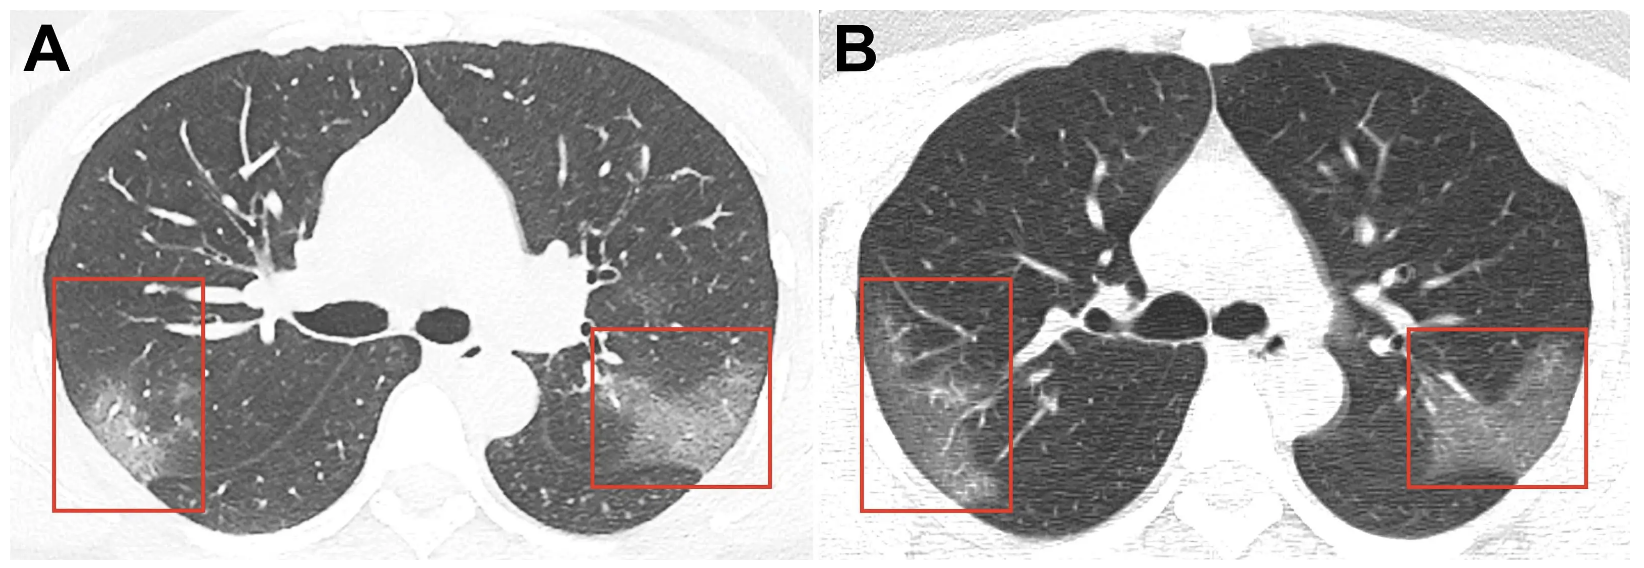

Өвчний урт хугацааны үр нөлөөг тогтооход арай эрт байгаа ч есөн өвчтөний уушгийг дурандахад цантсан шилтэй төстэй хэлбэрийн зүйл илэрчээ. Энэ нь уушгинд ямар нэгэн асуудал гарсныг илтгэж буй юм.